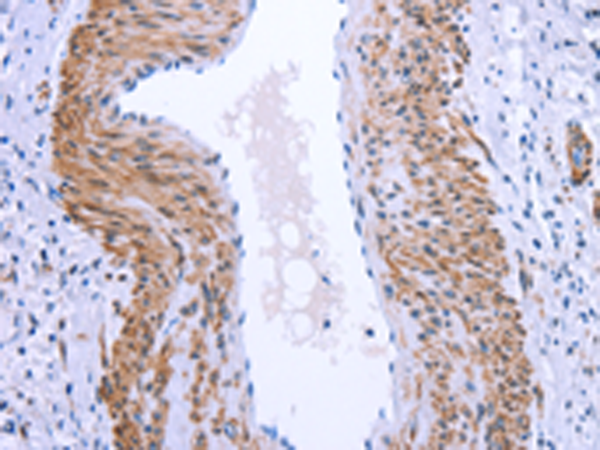

分类: 科研抗体货号: P04879别名: ATOD2应用: IHC反应种属: Human